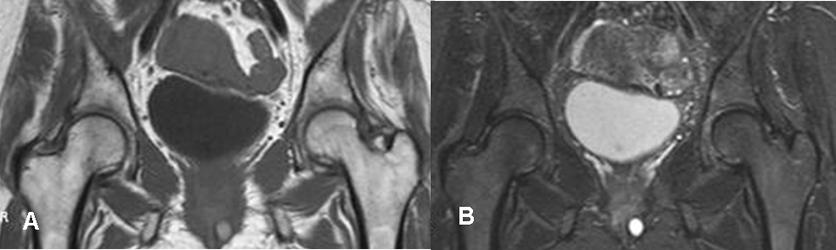

Fig 60. Osteoporosis transitoria.

A: RM coronal en T1 y B: RM coronal en STIR. Igual paciente anterior. Normalización de los cambios, después de 3 meses.